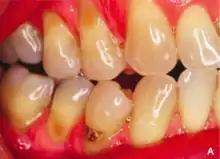

Abrasion is the non-carious, mechanical wear of tooth from interaction with objects other than tooth-tooth contact.[1] It most commonly affects the premolars and canines, usually along the cervical margins.[2] Based on clinical surveys, studies have shown that abrasion is the most common but not the sole aetiological factor for development of non-carious cervical lesions (NCCL) and is most frequently caused by incorrect toothbrushing technique.[3]

Abrasion frequently presents at the cemento-enamel junction and can be caused by many contributing factors, all with the ability to affect the tooth surface in varying degrees.[4]

The appearance may vary depending on the cause of abrasion, however most commonly presents in a V-shaped caused by excessive lateral pressure whilst tooth-brushing. The surface is shiny rather than carious, and sometimes the ridge is deep enough to see the pulp chamber within the tooth itself.

Non-carious cervical loss due to abrasion may lead to consequences and symptoms such as increased tooth sensitivity to hot and cold, increased plaque trapping which will result in caries and periodontal disease, and difficulty of dental appliances such as retainers or dentures engaging the tooth. It may also be aesthetically unpleasant to some people.[3]